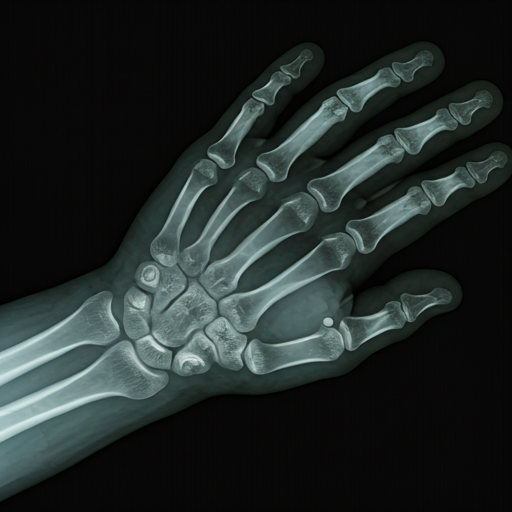

"Chẩn đoán tuổi xương là kỹ thuật đánh giá mức độ trưởng thành sinh học, phản ánh chính xác hơn tuổi sinh học so với tuổi thực. Kết hợp với các thông số nhân trắc, yếu tố di truyền và môi trường theo phương pháp chuẩn hóa Greulich & Pyle, quy trình cho phép dự báo chính xác chiều cao trưởng thành, giúp phát hiện sớm các bất thường về tăng trưởng."

AI phân tích chi tiết hình thái của từng xương riêng biệt trên phim chụp X-quang bàn tay và cổ tay, đánh giá mức độ cốt hóa với độ chính xác đến từng milimet, loại bỏ sai số cảm quan của mắt người.

Chụp X-quang chuẩn

Bàn tay không thuận tư thế thẳng đúng kỹ thuật.

Phân tích G&P

Chẩn đoán theo phương pháp Greulich & Pyle.